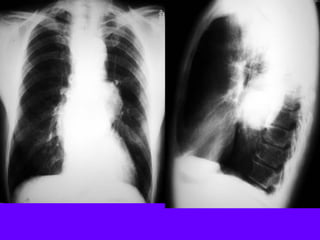

Necrotizing Pneumonia / Lung Abscess / Aspiration

Superior segment RLL dense pneumonia

Progression / Cavity